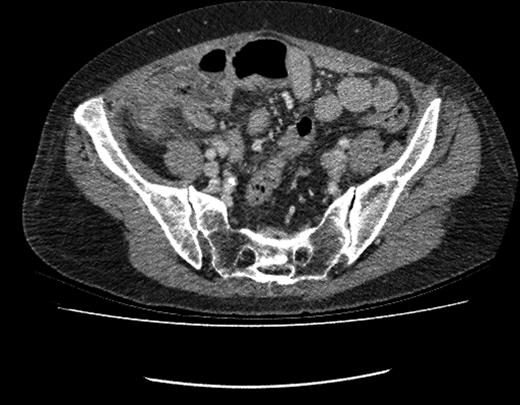

CT image showing fluid-filled appendix with peri-caecal fat stranding.

This patient returned to hospital 13 months following surgical resection of her gastric malignancy with an acute onset of abdominal pain. The patient gave a classical history of acute appendicitis with initial peri-umbilical pain, followed by localization of the pain to the right iliac fossa. Clinical findings and biochemical markers were consistent with this clinical suspicion. Prior to surgery a contrast-CT scan was performed. CT imaging indicated a fluid-filled appendix with peri-caecal fat stranding indicative of acute appendicitis. The patient consequently underwent an open appendectomy.